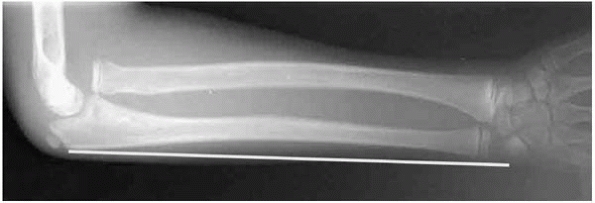

of dorsal angulation or 20 degrees of radial-ward angulation will yield

a good result. One way to stay out of trouble with parents is to put a

chart up in your office or cast room that shows progressive radiographs

of a distal radius fracture remodeling over the course of several

months (Fig. 7-6). This will help to decrease

anxiety in parents when the parents see the crooked bone on radiograph.

It will also help you avoid the temptation to overtreat these injuries.

![]() |

|

▪ FIGURE 7-6

Many pediatric orthopaedic practices hang a chart such as this one (from Children’s Hospital of Philadelphia) in their cast room to reassure parents and avoid overtreatment of distal radius fractures. |